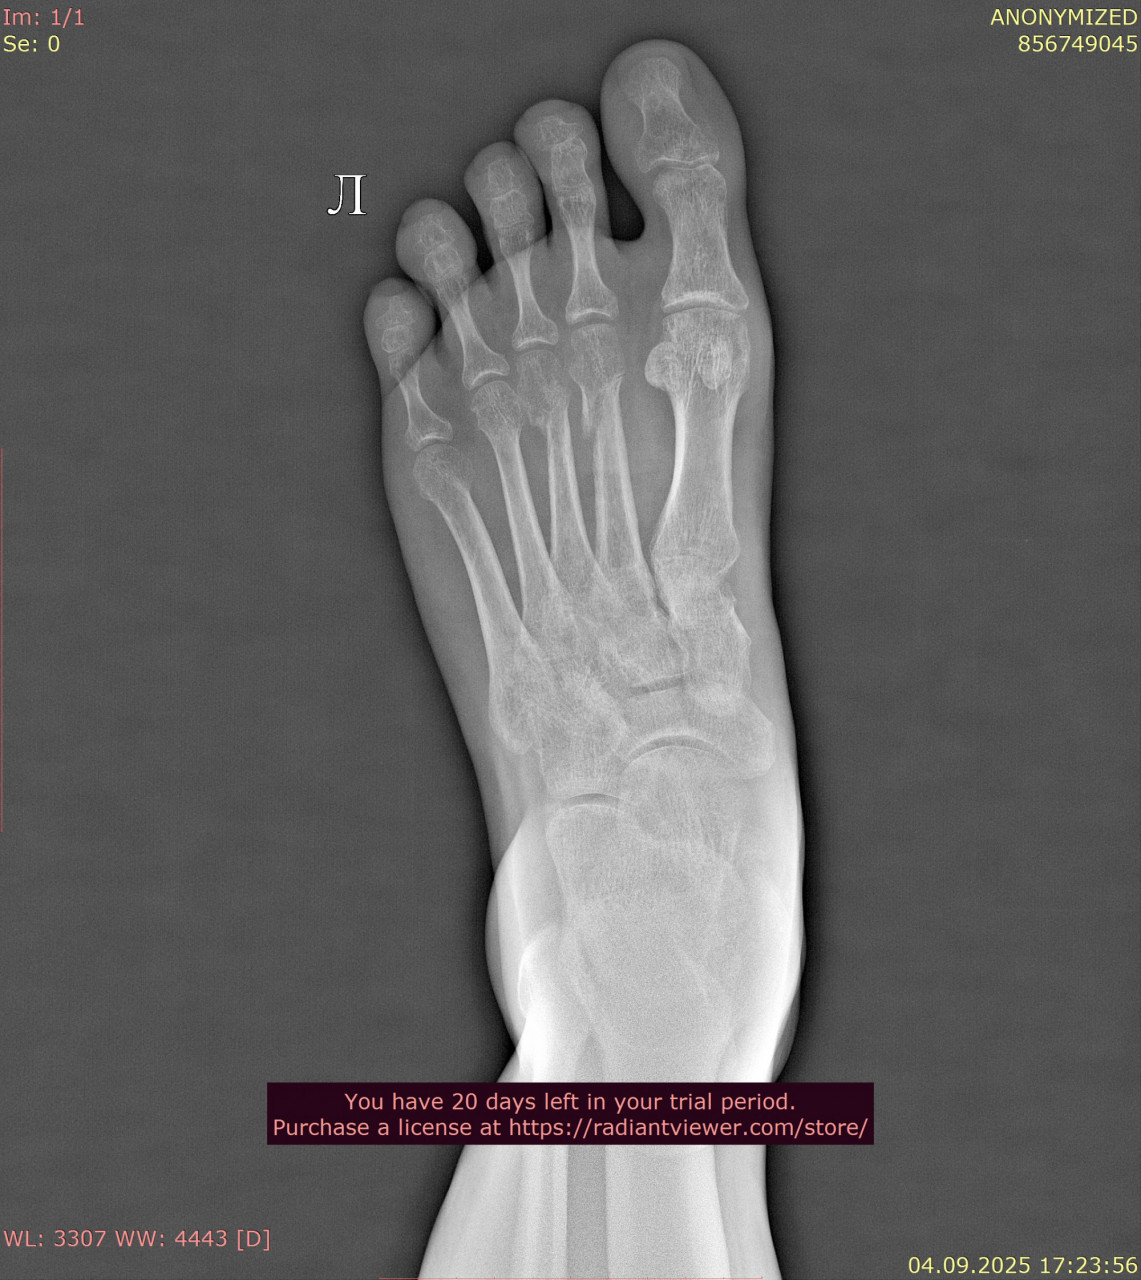

Посмотрите, пожалуйста, снимки стопы от 23.06.2025, когда был перелом, и спустя почти 11 недель от 04.09.2025. Как Вы считаете, переломы срослись нормально, или есть необходимость сделать еше один рентген в будущем? Можно ли переходить к обычному режиму нагрузок? У меня есть еще вторая проекция от 23.06.2025 и снимки голеностопного сустава, там тоже был перелом, но лимит сайта 3 файла. Остальные файлы могу прикрепить к Вашему ответу.

Здравствуйте. Судя по срокам и динамике на снимках, перелом срастается удовлетворительно, костная мозоль сформирована и переходить к постепенной нагрузке можно, но окончательное решение и необходимость повторного рентгена определяет ваш лечащий травматолог с учётом клиники и остеопении.